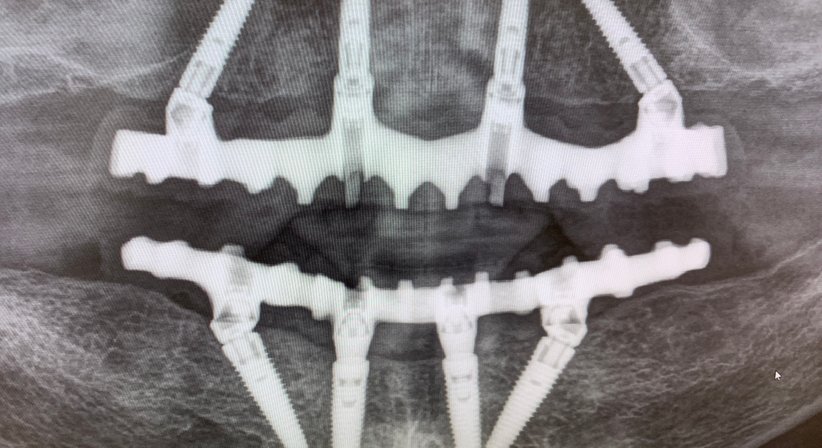

All-on-4 bietet Patienten neue Lebensqualität an nur 1 Tag. Das All-on-4 Konzept ist eine ganz spezielle, moderne und exklusive kieferchirurgische Behandlung, mit dem Ziel der kompletten Wiederherstellung eines oder beider Kiefer innerhalb von 24 Stunden. Das alles mit nur 4 speziellen Zahnimplantaten. Neues Lächeln über Nacht. Feste Zähne an 1 Tag. Weg von der Prothese! Oder am besten gar keine Prothese kennenlernen müssen. Das ist unser Ziel für Sie!

2. Einsetzen der 4 ganz speziellen Zahnimplantate